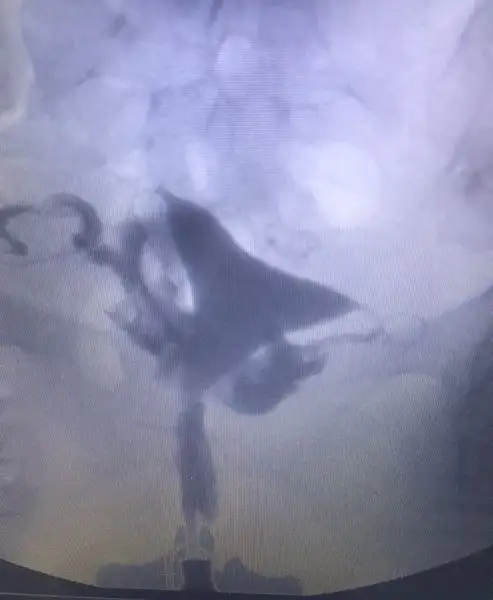

Aslında raporu alsam daha net olacak ama işte 1 haftaya çıkar ded bide acıbadem :) şişlikten bahsetmemişti doktor ama bilemedim şimdiHidroselpinks görüntüsü var gibi fotolarda ilerledikçe şişmeye başlamış sanki her iki tüpte de mevcut ama o kadar ileri düzeyde değil hidroselpinks

Şişlik dediğim fotoda ilerleyince oluşan beyaz görüntü varya sağda ve solda ondan bahsediyorum

Hidroselpinks deniliyor ona tüplerde tıkanıklık sonucu oluşan sıvının rahime sızıntı şeklinde akması iltihap yani

Ben anestezili çekildiğim için acıyı hissetmedim ama benimde gördüğüm kadarıyla ilaç iki tarafa da ulaşmış. Sizin filmde buna mı benziyrodu? İyi düşünüyorum zaten inşallah iyi de olacak sonuç :)Ben cekilirken doktor iki tarafta da aci var mi demisti. Sonra cekince baktim sizinki gibi rahmin 2 yanina ilac ulasmis kanallarin tamamen açık dedi. Ben suan sizinki icin öyle düşündüm. Açıldi demis sonuçta tıkanıklık. Iyi dusunun iyi olsun

Açık gibi gözüküyor canım bende çektirdim benim sol kapalı sağ ucundan kapalı çıktı sen be kadara çektirdin acabakızlar selamlar rahim filmi görüntülerini ekliyorum bilgisi olan yardımcı olur mu?

Aynen kapalı olanlarda baya belli oluyor. Benim ilaç gitmiş gibi görünüyor. Anestezili 800 e çekilde benimkiAçık gibi gözüküyor canım bende çektirdim benim sol kapalı sağ ucundan kapalı çıktı sen be kadara çektirdin acaba